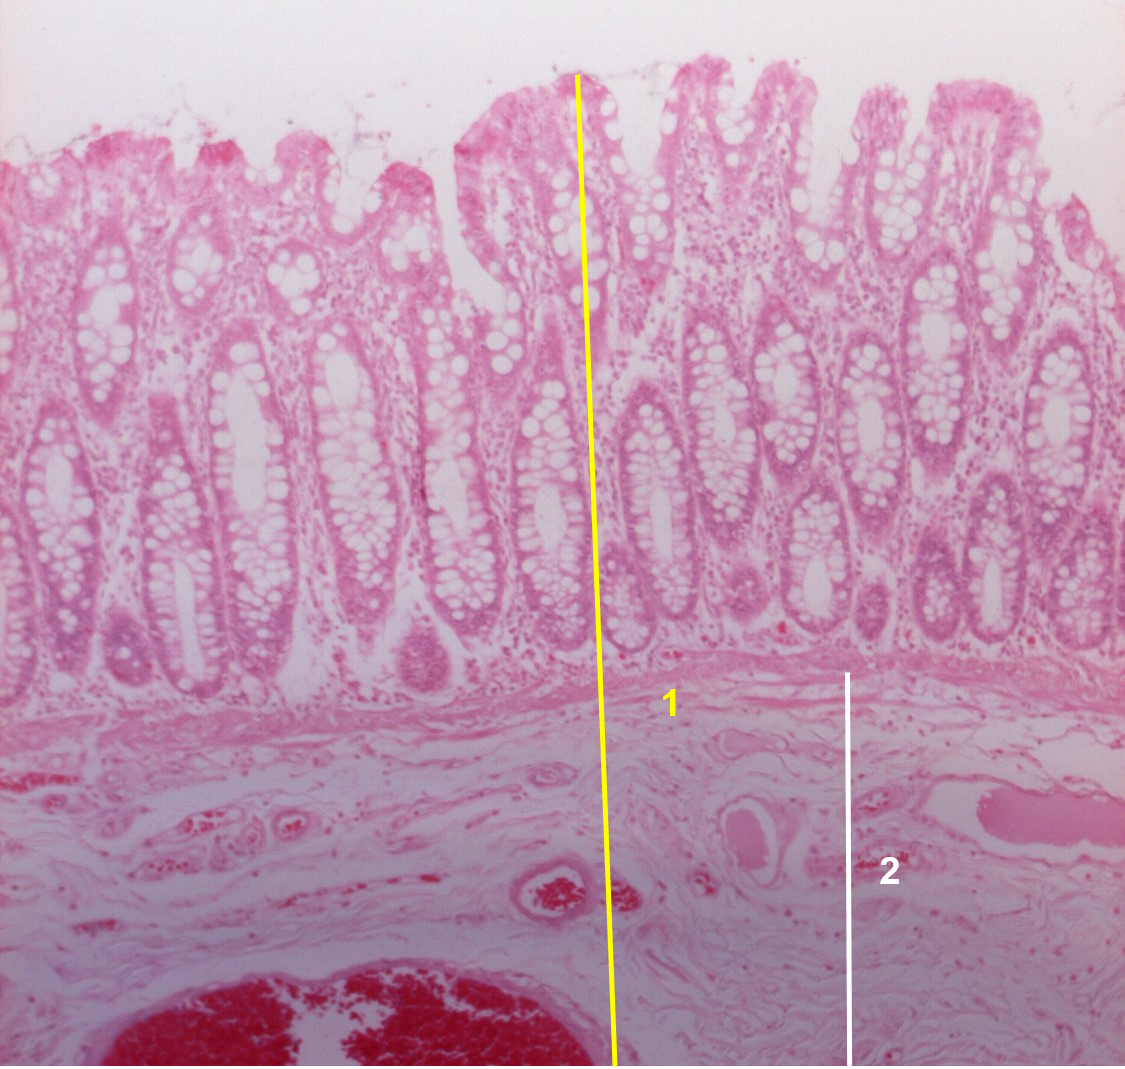

1: Cólon

2: Submucosa - Tecido conjuntivo laxo